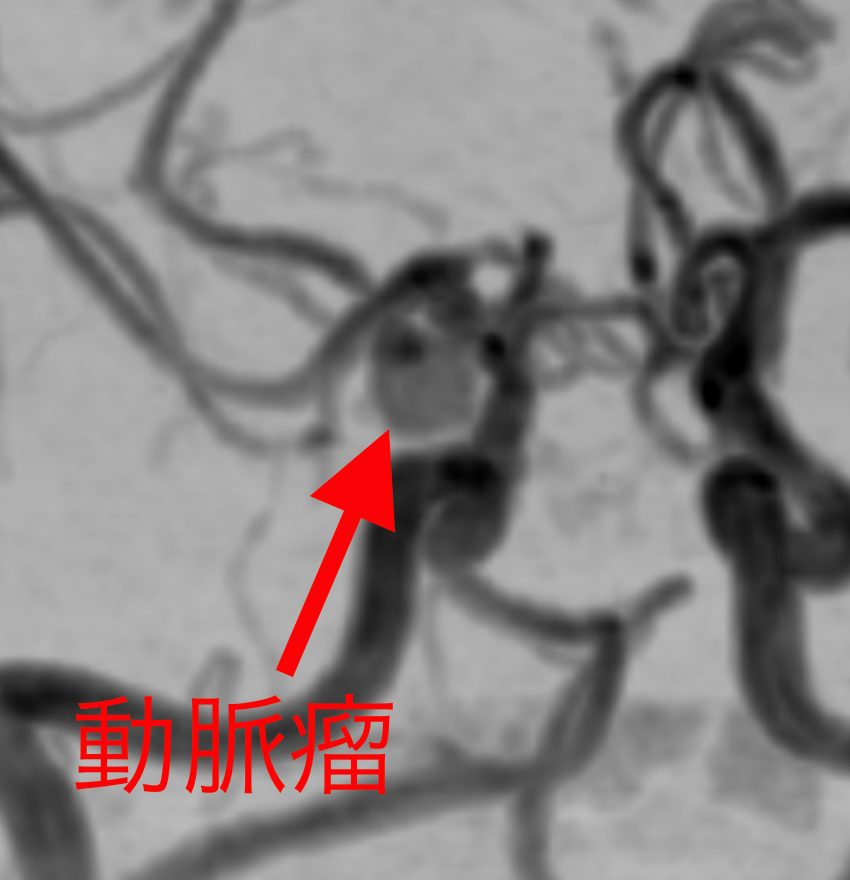

もし、脳卒中になってしまったら、残念ながら現在の医療では完全に治す事はできません。しかし、脳卒中は発病する前に予測して予防する事ができます。たとえば、くも膜下出血は脳内の動脈瘤が破裂して起こる病気ですが、MRI検査で破裂する前の動脈瘤を発見する事が可能です。だからこそ、健康だと思っている今、MRI検査で予防につなげる事が大切です。

未破裂脳動脈瘤

破裂した場合くも膜下出血を起こし、突然死する場合もあります。未然に発見して手術を行い、防ぐ事が可能です。